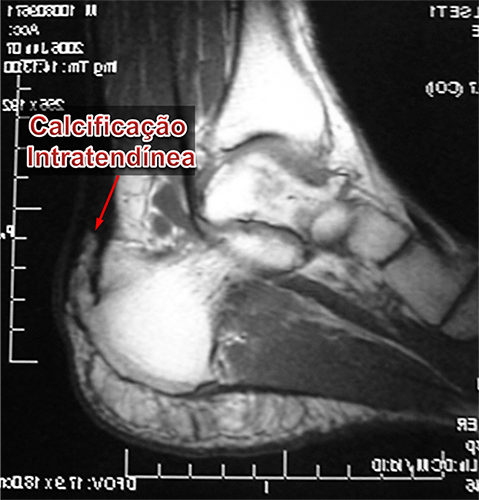

Calcificação Intratendínea (Esporão do Tendão de Aquiles) :

A calcificação intratendinea, popularmente chamada de esporão do tendão de Aquiles, forma-se por uma alteração celular degenerativa das fibras do tendão. Isto ocorre pela alternância, durante um longo período de tempo, entre os processos de inflamação, microrruptura e reparo local. Portanto, a constante tentativa de cicatrização de uma lesão crônica do tendão leva à sua degeneração e calcificação local de suas fibras.

Embora a ultrasonografia seja útil no diagnóstico de doenças tendíneas, a ressonância nuclear magnética é o melhor exame para avaliar as condições teciduais do tendão de Aquiles, possibilitando visualizar o grau e a extensão do processo degenerativo, calcificações e pequenas rupturas com melhor definição e maiores detalhes.